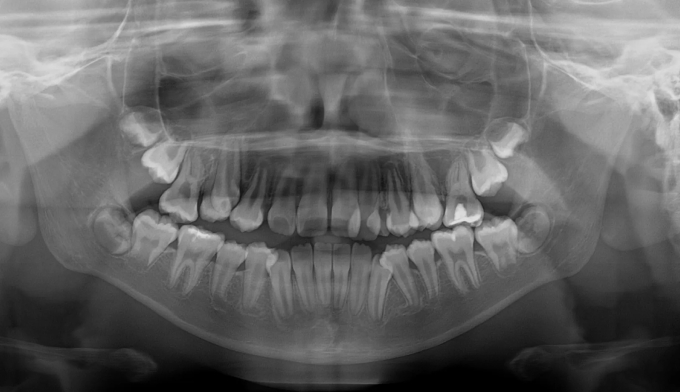

너무 좁은 위턱 공간으로 인해 치아의 맹출 순서가 어긋나버렸습니다.

송곳니가 원래 나와야 할 공간이 없다보니 작은 어금니 위치로 이동해서 맹출하고 있습니다. 이를 치아 전위라고 합니다.

이와 더불어 좁은 위턱 악궁은 얼굴 전체의 비대칭을 유발하고 있고, 아래턱의 과성장은 주걱턱 경향까지 보이고 있습니다.